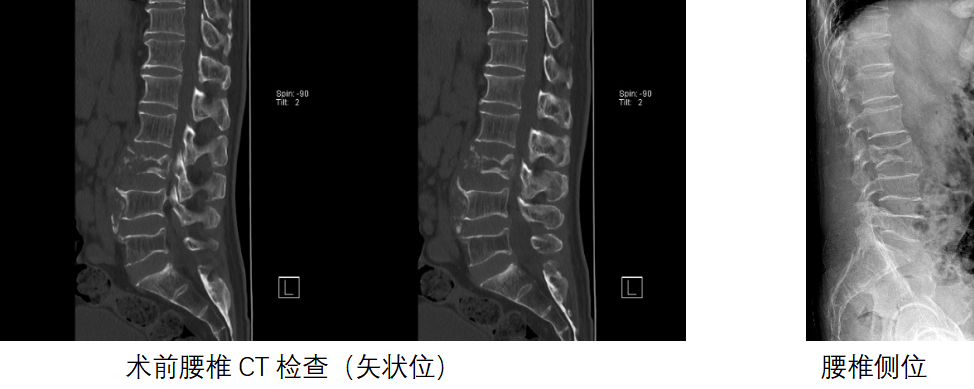

腰椎CT:L3椎体骨质广泛破坏,椎体前中柱压缩骨折,椎体后壁不完整,骨折块后移。椎弓根形态尚可

影像学资料提示患者腰椎病理性骨折压迫神经,仅短短一个月,L3椎体骨质破坏严重,双下肢肌力0级。综合考虑原发肿瘤类型、转移灶生物学行为、患者全身状况、手术耐受性、预期生存期等多重因素,科室为保障手术安全开展,制定完整手术预案,进行多学科会诊(MDT)。